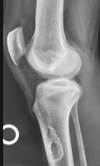

Fratura do platô tibial lateral - Schatzker tipo 2 (traço de fratura + depressão do plato lateral).